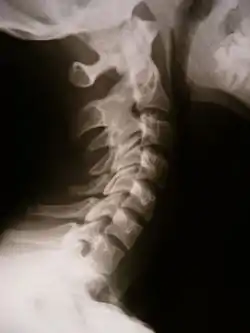

![]() Синостоз - рентгенограма шийного відділу хребта | |